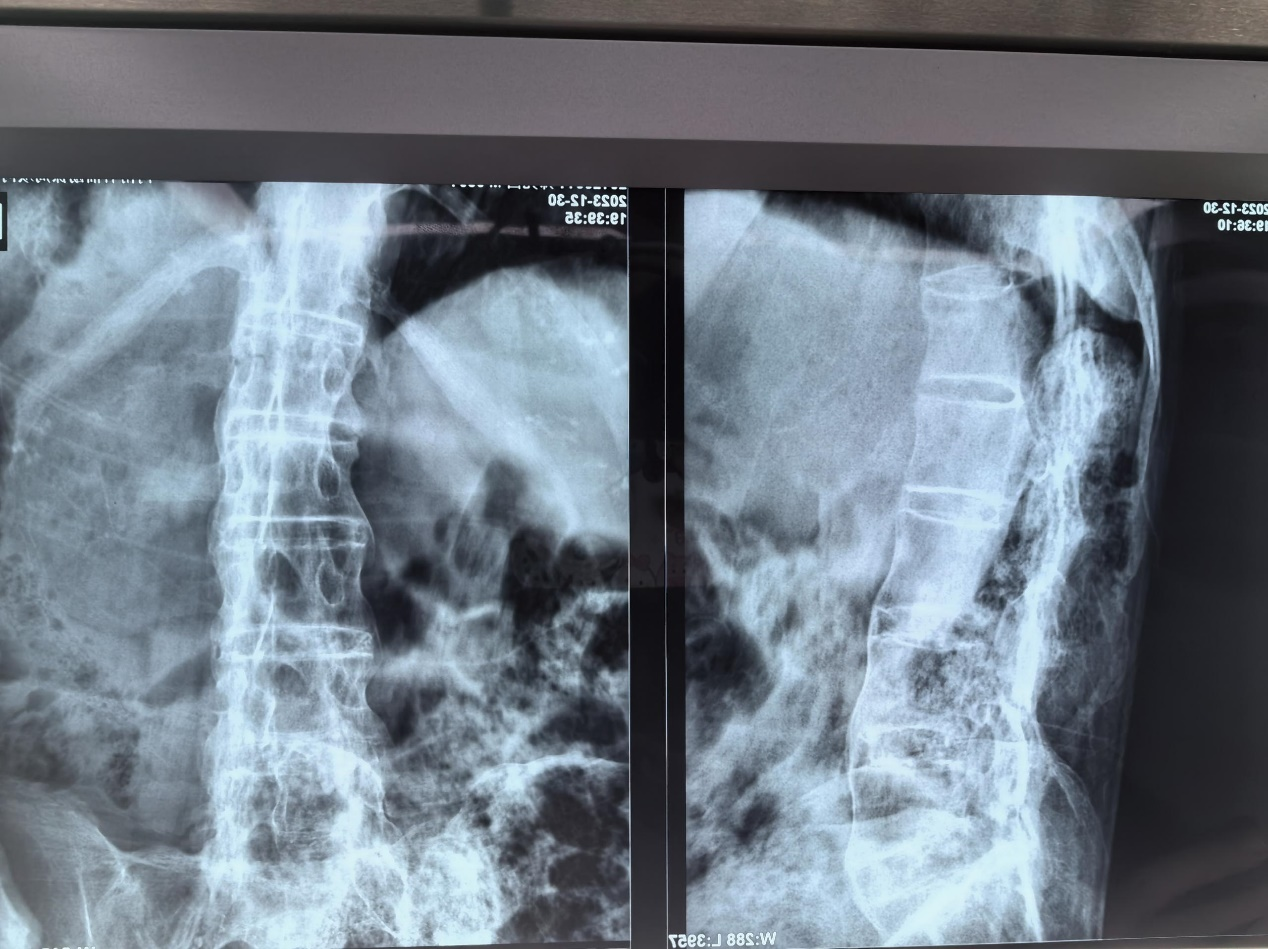

患者强直性脊柱炎既往病史,股骨粗隆下骨折。

强制性脊柱炎多年已出现椎体融合

强直性脊柱炎引起髋关节间隙变窄,屈髋畸形,骨折断端移位大,复位困难。